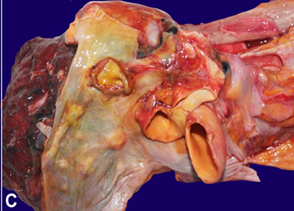

subclavian vessels. There were multiple tumour nodules seen at the pericardial

pleura ranging from 0.5cm to 1.5cm in diameter (figure 1c). The tumour

C

- pericardial surface with multiple greyish-white tumour nodules (black arrows).